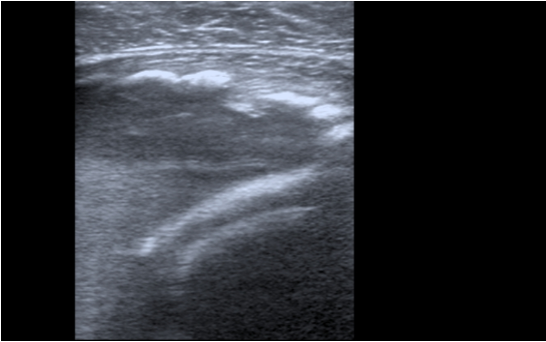

Hematoma no encapsulado de 5 x 9 cm en vasto intermedio, sin captación de doppler color y con aparición en bordes externos de calcificaciones con sombra acústica posterior.